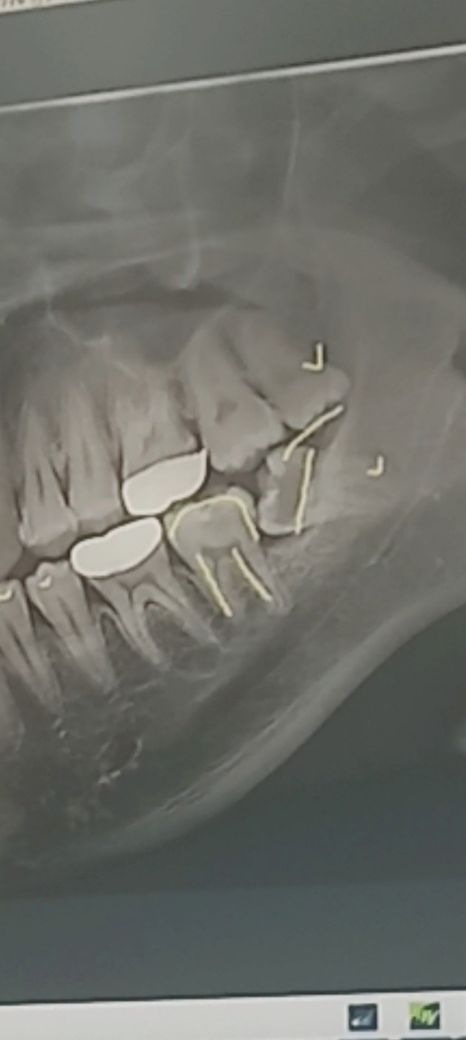

제 아랫 쪽 사랑니 난이도가 어떻게 되나요?

우선 제 문제의 사랑니 사진입니다.

제가 치과를 너무 무서워하는데 사랑니를 뽑으려니깐 더 겁이 나더라구요... 이 정도면 아래 쪽 사랑니

난이도가 어떻게 될까요 선생님...?

기울어진 사랑니의 경우에는 난이도가 높은 발치에 속합니다.

치아를 발치할경우 치아를 자르면서 제거를 하게 됩니다.

방향이 기울어서 나는 매복사랑니의 경우 바로 앞 어금니에 걸리게 됩니다. 따라서 누운 사랑니를 그냥 두면 바로 앞 어금니를 상하게 하는 경우가 많기에 가능한 빠른시일내에 발치를 하는 것이 좋습니다.

난이도가 크게 높은건 아닌거 같습니다. 완전 매복치아가 아니기떄문에 치아 머리를 삭제하고 발치를 하시면될것같습니다.

1. 일반적인 수술발치(잇몸을 절개하여 열고 사랑니를 뽑는 발치) 수준의 난이도 입니다.

2. 다만 아래턱의 큰 신경이 지나는 길이 있는데 근접해 있으므로 추가적으로 위치 등을 확인하기 위해 CT를 찍어봐도 좋을 것 같습니다.